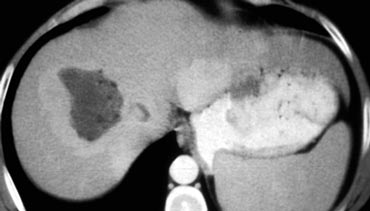

Large HCC with mozaik pattern in a non cirrhotic patient. Large HCC with mozaik pattern in a non cirrhotic patient.

Late appearance of HCC

HCC is a silent tumor, so if patients do not have cirrhosis or hepatitis C, you will discover them in a late stage.

They tend to be very large with a mozaic pattern, a capsule, hemorrhage, necrosis and fat evolution.

HCC becomes isodense or hypodense to liver in the portal venous phase due to fast wash-out. On delayed images the capsule and sometimes septa demonstrate prolonged enhancement.